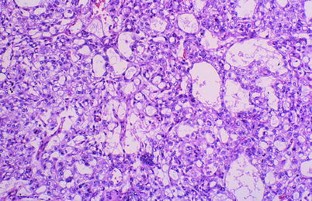

Fig. 2